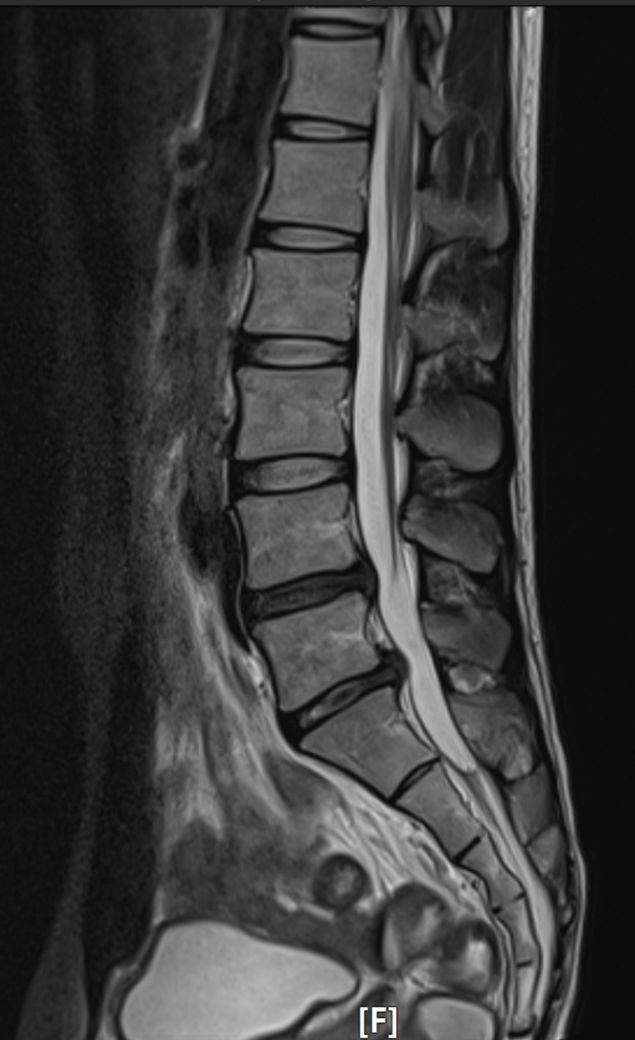

21년 3월부터 다리를 들어올릴때 엉덩이 위쪽에 통증이 있었는데 대수롭지않게 여기고 진료를 안보다가 21년 8월에 운동하는데 통증이 심해져서 병원을 갔습니다. 그 결과 L4-L5와 L5-S1 디스크에 퇴행성 소견이 보이고 L5-S1가 탈출됐다는 진단을 받았습니다.

mri사진 첨부했습니다. 모바일에서만 보이네요ㅜㅜ